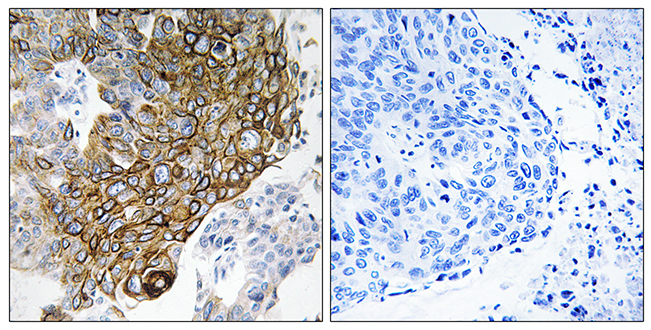

Anti-MCM4 AntibodyA97780

ApplicationsWestern Blot, ELISA, ImmunoHistoChemistry

ReactivityHuman, Mouse

Anti-JAK2 AntibodyA97781

ApplicationsELISA, ImmunoHistoChemistry

ReactivityHuman, Mouse, Rat